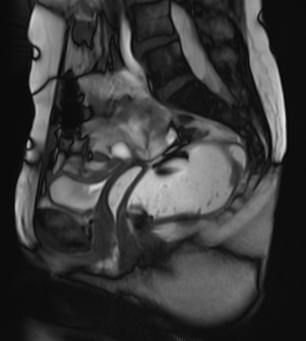

Pelvic floor MRI (Magnetic Resonance Defaecating Proctography) is a specialised scan that uses magnetic fields to create images of your pelvic organs and muscles, allowing our team to see how these structures move when you're relaxing, straining, and passing a bowel motion. The scan is non-invasive, painless, and does not use radiation.

Pelvic floor MRI allows doctors to assess both the pelvic organs and the support structures (muscles and ligaments), and to identify problems such as prolapse, blocked bowel emptying (obstructed defaecation), internal folding of the bowel (intussusception), or problems coordinating the pelvic floor muscles (dyssynergia).